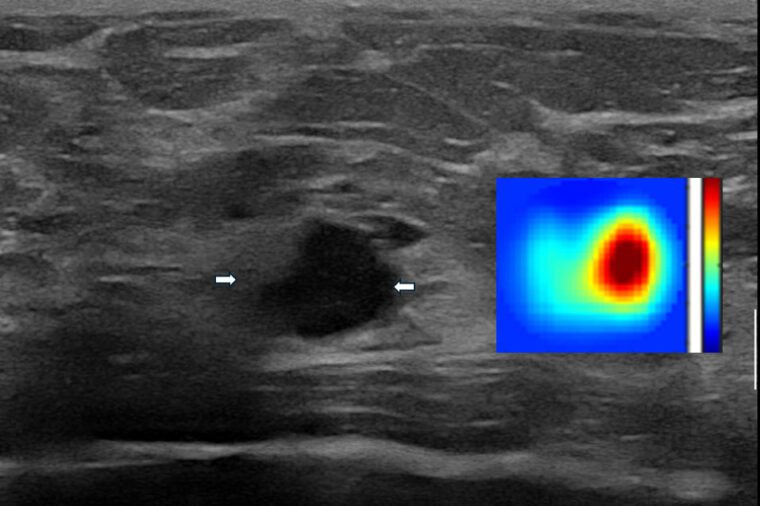

Zhu and her team have pioneered this noninvasive imaging technique that uses near-infrared light to create 3D pictures of tissues, revealing functional differences between normal and cancerous tissue of blood vascular contrast and oxygen levels. The technology, when combined with standard-of-care ultrasound evaluation, can significantly triage low-risk breast lesions regarding biopsy. Considering that there are more than 1 million annual breast biopsies in the United States each year, a 25% biopsy reduction could have a significant impact on saving health-care costs and patient anxiety, Zhu said.

"With diffuse optical tomography, the resolution is lower because light is scattered in the tissue," Zhu said. "Because of the ultrasound localization, we avoid the uncertainty and improve diffuse optical tomography."

The team studied 226 patients with a breast lesion with a likelihood of malignancy and imaged them with ultrasound-guided diffuse optical tomography prior to their standard-of-care, ultrasound-guided biopsy. The ultrasound-guided diffuse optical tomography provided total hemoglobin concentration maps and blood oxygen saturation levels to the study radiologists for reconsidering their biopsy decision. Hemoglobin, which is carried by red blood cells, absorbs the near-infrared light. A higher level of hemoglobin raises suspicion for cancer. Blood oxygen saturation, or the amount of oxygen in the blood, is another biomarker for indicating tumor metabolism. A lower level of blood oxygen saturation is indicative of suspicion for cancer.

The total hemoglobin concentration of patients with a malignant tumor was significantly higher than that of all benign lesions, the researchers found. The blood oxygen saturation was significantly lower in malignant lesions than in benign lesions. In addition, total hemoglobin concentration was significantly higher in grade 3 cancerous lesions than in grades 1 and 2, while the blood oxygen saturation was significantly lower. While the blood oxygen saturation of cancerous lesions smaller than 2 centimeters was not significantly different from that of cancerous lesions larger than 2 centimeters, the blood oxygen saturation differed significantly between the benign and malignant groups.